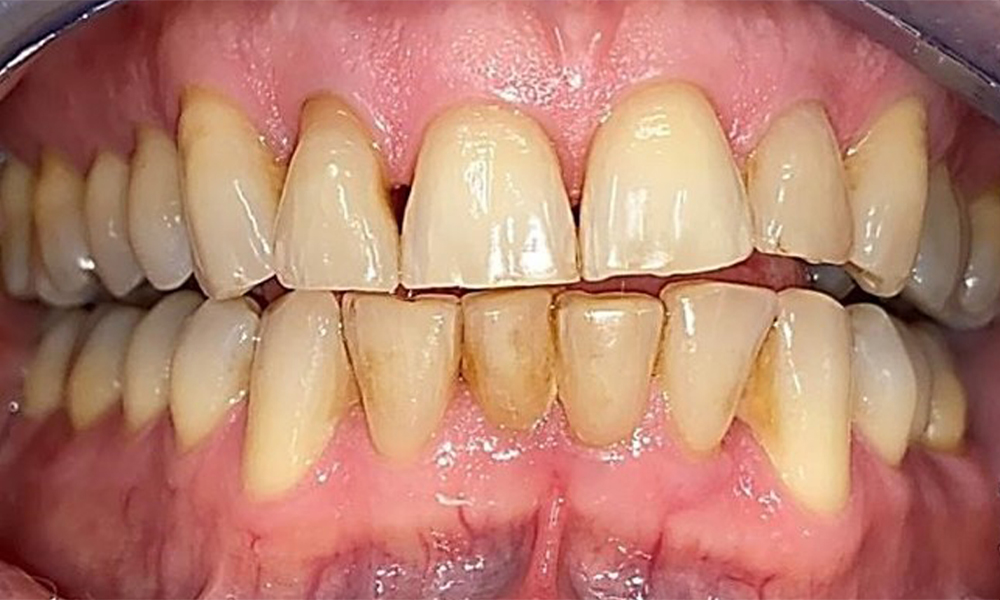

Frontalansicht mit Verlust der interdentalen Papille zwischen 12 und 11. © Dr. R. Krapf

Abb. 2 Frontalansicht mit Verlust der interdentalen Papille zwischen 12 und 11. © Dr. R. Krapf

Der Patient hat ein vollbezahntes Gebiss mit 28 Zähnen, an welchen sich im Molaren- und Prämolarenbereich Amalgamfüllungen und Compositefüllungen befinden. An Zahn 14 zeigt sich ein sichtbarer klinischer Randspalt. Zahn 27 hat ein suffizientes Goldinlay. Zudem zeigen sich generalisierte Attritionen und Abrasionen. (Abb. 2, Abb. 3, Abb. 4, Abb. 5, Abb. 6)

Der Patient hat eine Parodontitis Stadium II, Grad B (5). Die klinischen Sondierungstiefen liegen mit 1-3mm im physiologischen Bereich. Lokalisierte Sondierungstiefen finden sich an 17 und 27 jeweils mesiopalatinal mit 5mm. Es liegen generalisierte Rezessionen von 1-3mm vor mit partiellem Verlust der Interdentalpapillen (Abb. 2, Abb. 3, Abb. 4)